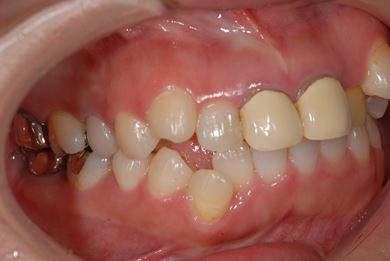

| 性別/年齢 | 女性 / 31歳 | ||||||||||||||||||||||||||||||||

| 治療方針 | セラミック治療により、審美的回復を行う。 | ||||||||||||||||||||||||||||||||

| 治療内容 | CAD/CAMオールセラミッククラウン1本(オールセラミック用土台1本)、オールセラミッククラウン2本(オールセラミック用土台2本) | ||||||||||||||||||||||||||||||||

| 総治療費 | 341,775円 | ||||||||||||||||||||||||||||||||

| 治療期間 | 10ヶ月 |